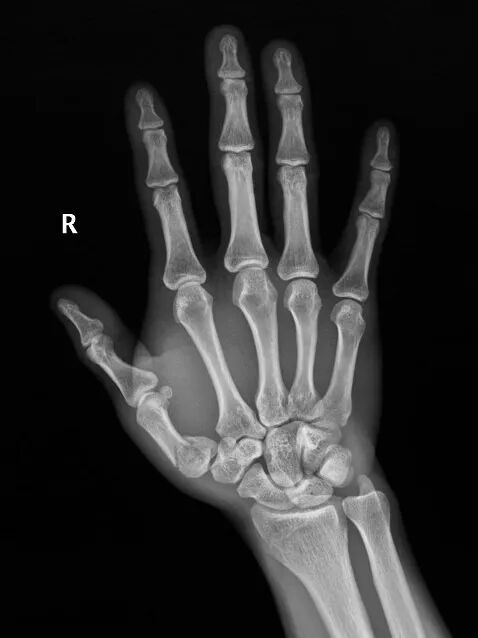

患者是52歲男性,因摔倒導致右手第一掌骨基底部骨折

手術前右手正斜位片

手術后次日復查左手正斜位片